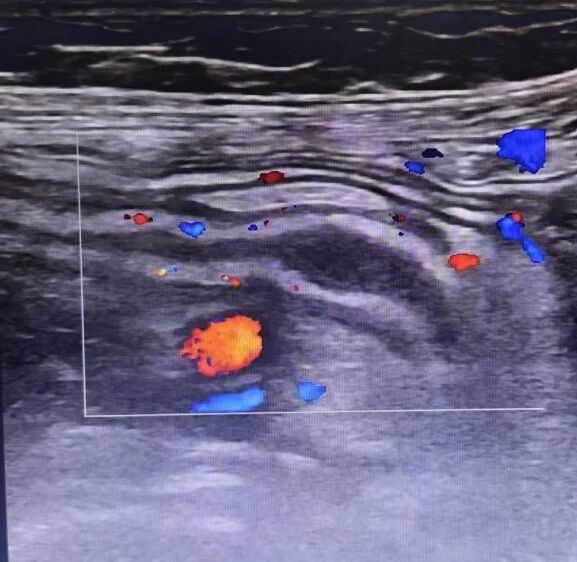

1.急性阑尾炎:超声可显示肿胀的阑尾、周围渗出及粪石,是诊断的重要依据。

阑尾炎超声影像